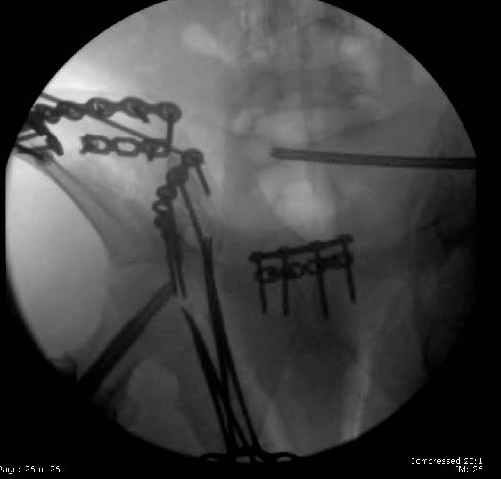

Here are the postop fluoros.

First exposed symphysis & clamped w/Faraboeuf as close to anatomic as possible.

Then extended to R ilioinguinal,really just the lateral window.

Reduced the triangular wedge piece of iliac wing to posterior intact ilium (crescent), held w/k-wire, then used 3-hole push plate to keep from moving, lagged from lat-med w 3.5 screw.

Then 6-hole plate along brim with 1 screw in R sacral ala. Then lagged 2 screws along crest A --> P. finally 10-hole plate along inner aspect of crest. R posterior ilium still a bit stepped off.

Symphysis then 'fine-tuned' & reduced as close as possible to anatomic (but, still with forward rotation of R hemipelvis - or, is it extension?) Accepted that amount of deformity and plated symph

with 4-hole symphyseal plate.

Fluoroed L SI joint and it seemed stable, but wide. So, applied c-clamp to try to squeeze down L SI joint (and note, on the last slide attached, that it's still wide), and got it closer. Single perc Iliosacral screw 40mm thread.

Applied second plate anteriorly on symphysis as I wasn't confident L SI was as stable as it could be and wanted to protect it better.